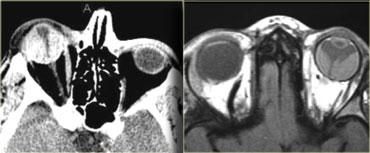

Hãy quan sát hình ảnh bên trái trước.

Bên nào bất thường và chẩn đoán có khả năng nhất là gì?Có hình ảnh thiểu sản cánh xương bướm bên phải và bên trái thần kinh thị giác gần giao thoa thị giác bị phì đại (thấy rõ trên MRI).

Do đó chẩn đoán là bệnh u xơ thần kinh type I (NF-1) với thiểu sản cánh xương bướm và u thần kinh đệm đường thị giác.Thuật ngữ “u thần kinh đệm thị giác” thực ra không hoàn toàn chính xác.

Trên thực tế, u có thể xuất hiện ở bất kỳ vị trí nào dọc theo đường thị giác, từ vùng chẩm đến giao thoa thị giác và thần kinh thị giác.

Thuật ngữ “u thần kinh đệm” cũng khá không đặc hiệu.

Các u này là u tế bào hình sao lông mao thể trẻ (juvenile pilocytic astrocytoma) WHO độ 1, là dạng lành tính nhất của u tế bào hình sao.

Chúng chiếm 4% tổng số u hốc mắt.

Hơn 50% bệnh nhân có u thần kinh đệm thị giác mắc bệnh NF1, nhưng trong số bệnh nhân NF1 chỉ khoảng 10% có u thần kinh đệm thị giác.

U ít có dạng nang hơn trong NF so với không có NF.

Tuổi trung bình khi chẩn đoán là 4-5 tuổi và chỉ 20% bệnh nhân có triệu chứng thị giác, vì u thần kinh đệm không ảnh hưởng đến thần kinh thị giác sớm và vì trẻ nhỏ không phàn nàn về vấn đề thị lực.Bên trái là một trường hợp khác với hình ảnh điển hình hơn của u thần kinh đệm thị giác cũng ở bệnh nhân NF1.